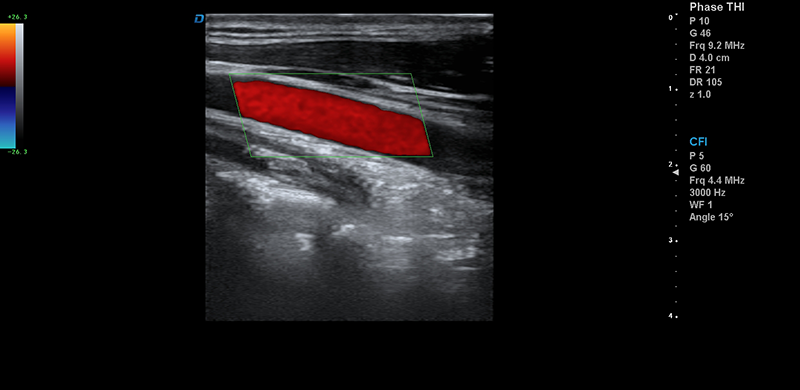

IMT血管內中膜自動測量:血管內中膜的厚度是預測無臨床癥狀的人群患心血管疾病風險的重要指標,大為自動內中膜測量技術為您提供了有效的檢測工具,自動測量血管近場和遠場內中膜的厚度,自動優化測量的角度。

諧波成像(THI)、諧波融合成像(FHI):THI和FHI比傳統的信號處理得到的信號強度增加30%以上,降低了噪聲和偽像,大幅度提高組織圖像的分辨力